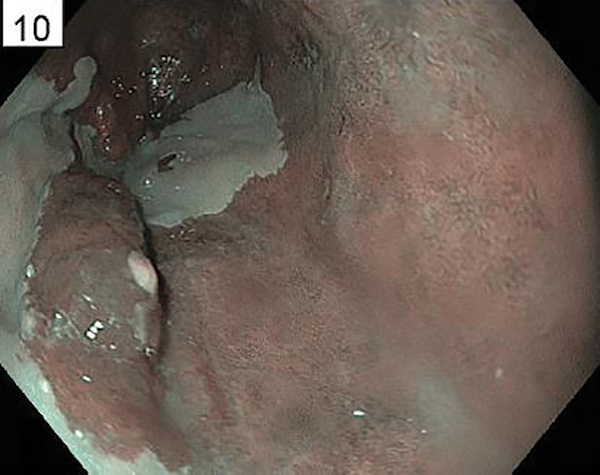

A 45-year-old man is undergoing surveillance for a prior diagnosis of Barrett’s with low-grade dysplasia at another center. The pathology has subsequently been confirmed by a recognized expert GI pathologist. You have elected to repeat the endoscopy that reveals the findings in FIGURES A and B. Which of the following is the optimal management at this time?

A. Proceed with radiofrequency ablation (RFA) for confirmed low-grade dysplasia.

B. Obtain wide area transepithelial sampling to improve the accuracy of diagnosing Barrett’s esophagus.

C. Perform endoscopic resection of the focal lesion noted at endoscopy.

D. Obtain targeted biopsies of the focal lesion noted at endoscopy.

E. Perform confocal endomicroscopy of the focal lesion noted at endoscopy.